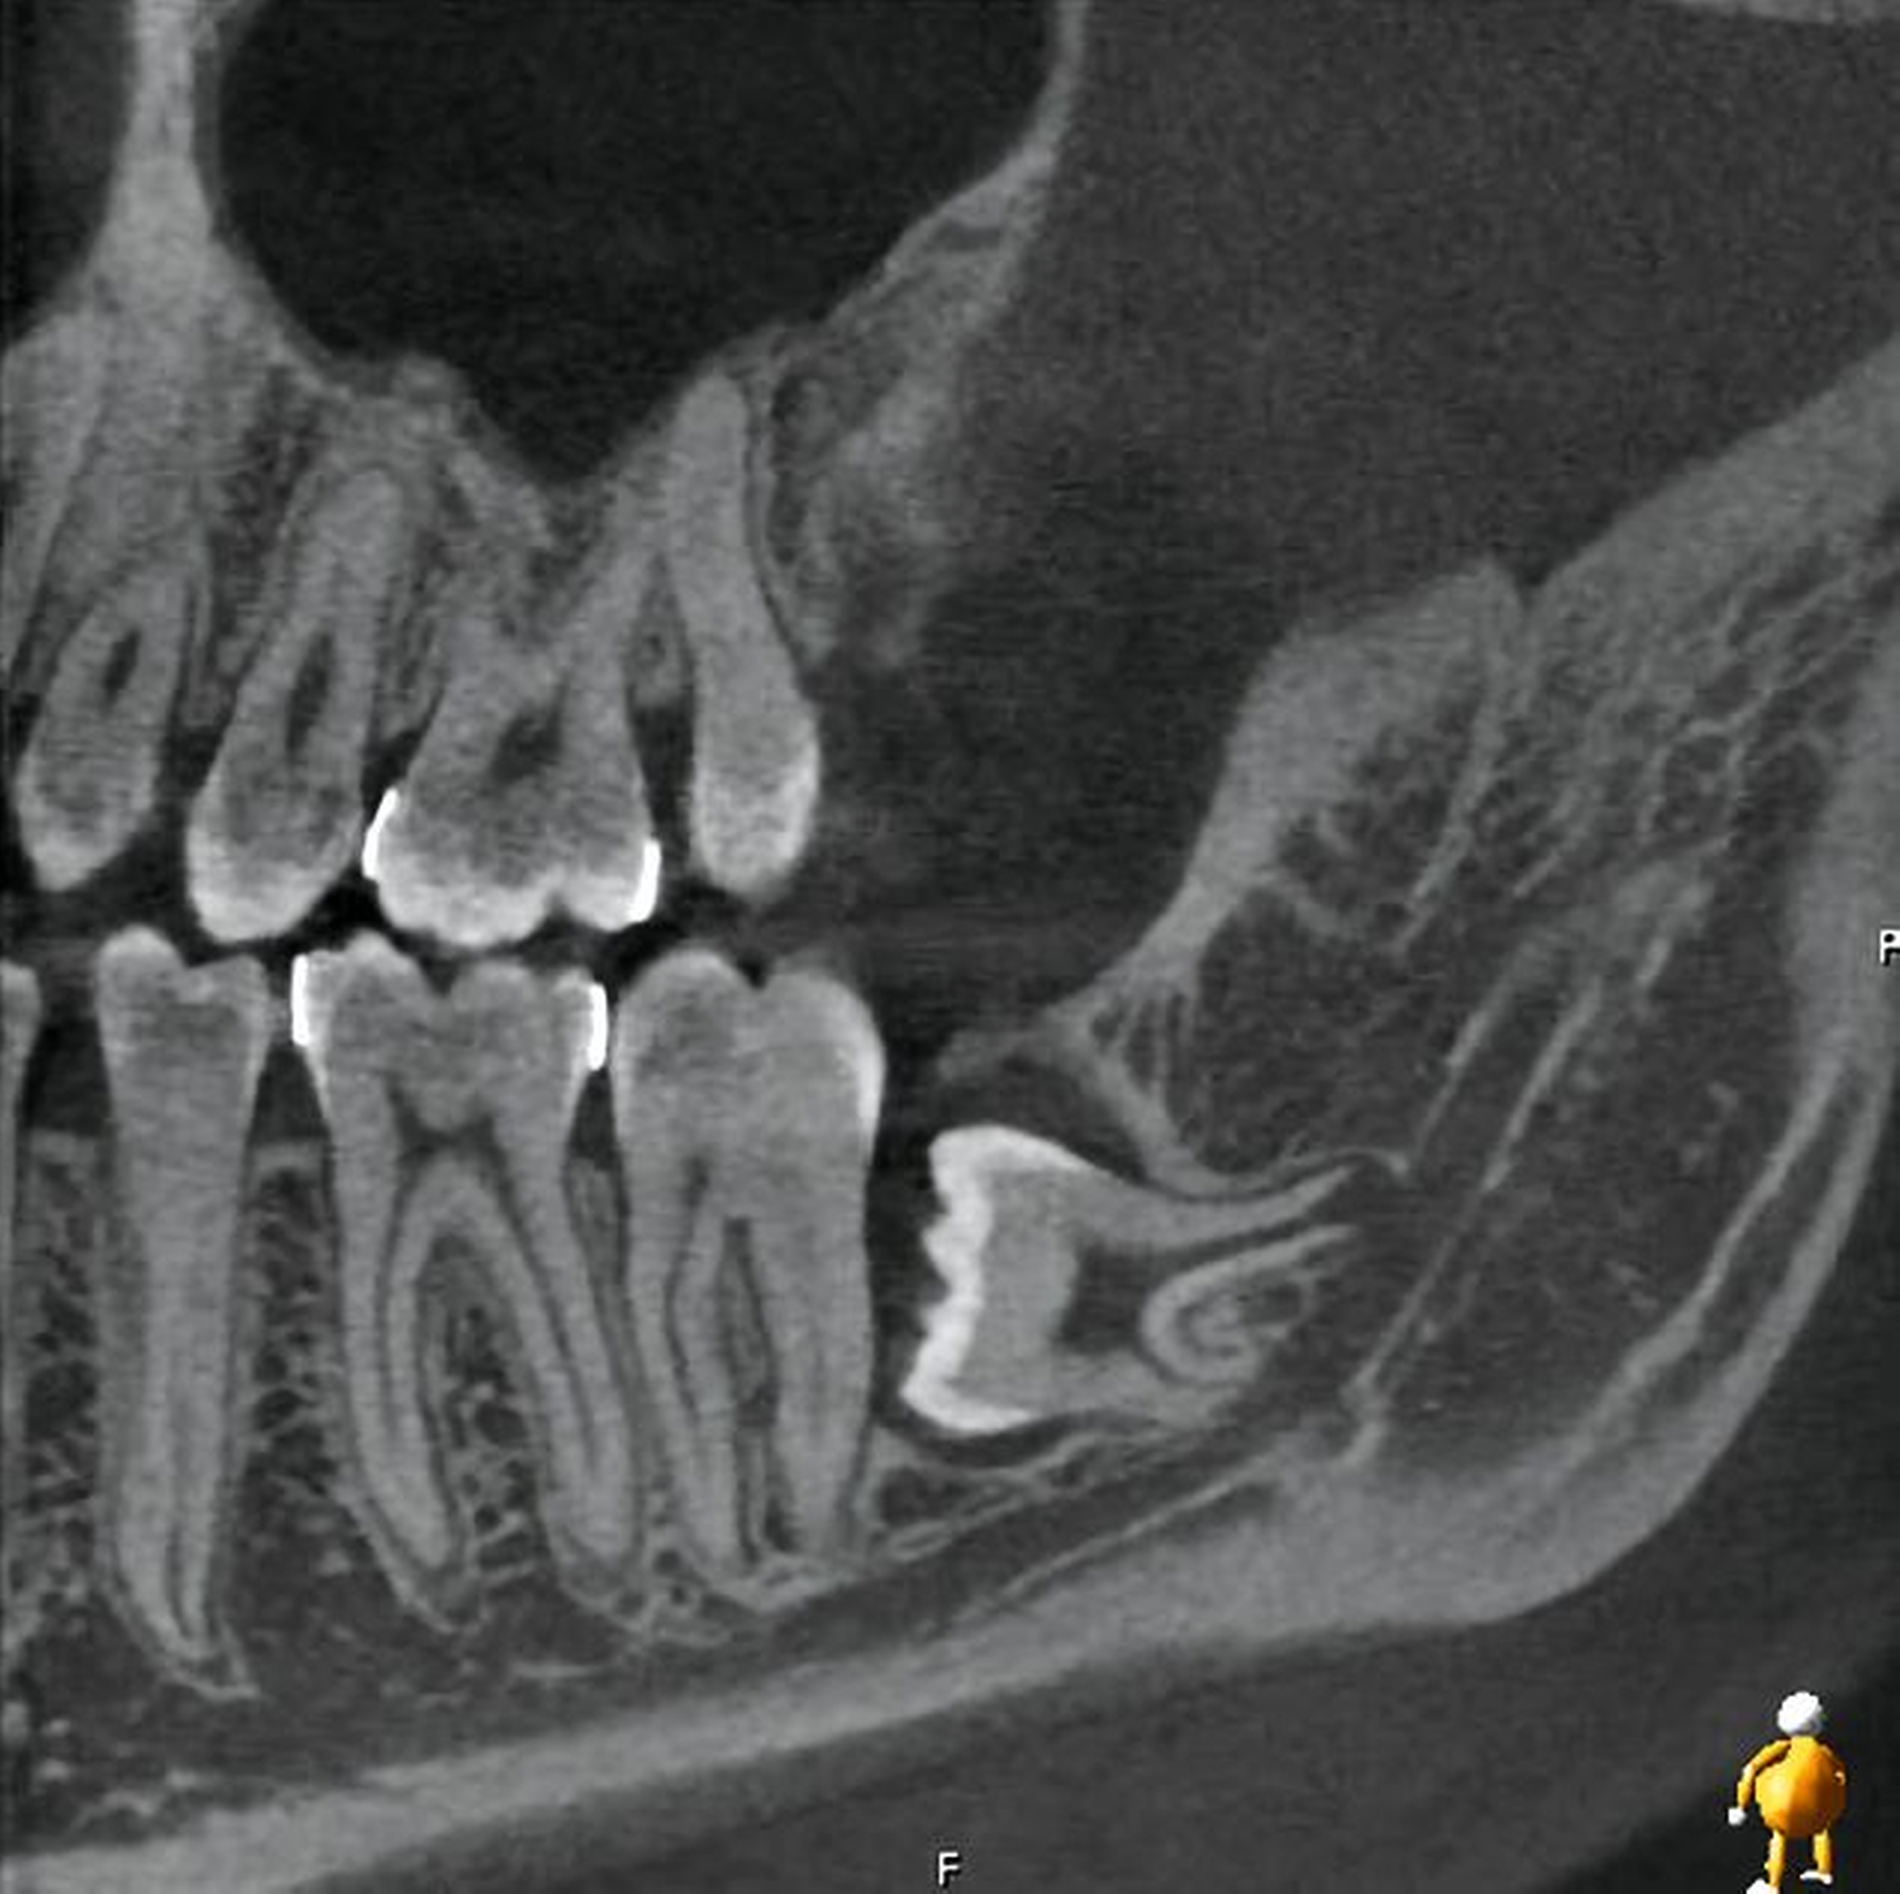

Im vorliegenden Fallbeispiel wurde eine dreidimensionale Bildgebung durchgeführt, da sowohl im Ober- als auch im Unterkiefer Risikohinweise bestanden. Zum einen lag eine unmittelbare Lagebeziehung zum N. alveolaris inferior und somit ein erhöhtes Risiko einer Nervschädigung vor, zum anderen bestanden Hinweise auf Lageanomalien und mögliche Doppelanlagen im Oberkiefer, die in der zweidimensionalen Bildgebung kaum beurteilt werden konnten. In der DVT zeigte sich in Regio 48 ein intraradikulärer Verlauf des N. alveolaris inferior durch die Wurzel des nach mesial gekippten und retinierten Zahnes 48 sowie eine perikoronare Aufhellung, die nah an die distale Wurzel des Zahnes 47 reicht (Abbildung 2).